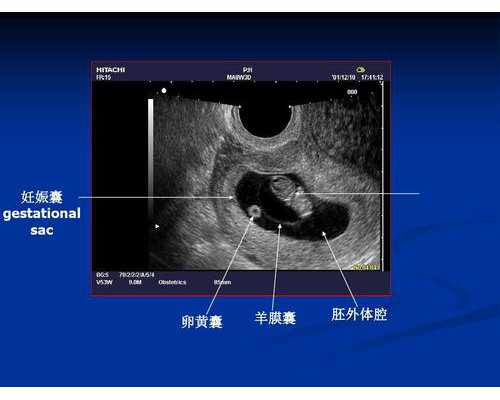

- 5周要求:孕妇需要见到卵黄囊,超声波检测显示宫内早孕5周+,即可进行测试。

- 6周要求:满6周,且见到心管搏动,就能进行测试。

- 7周要求:孕妇的胚芽 (CRL) 需达到9mm以上或孕囊 (GS) 需达到35mm,且见到心管搏动,才可进行测试。